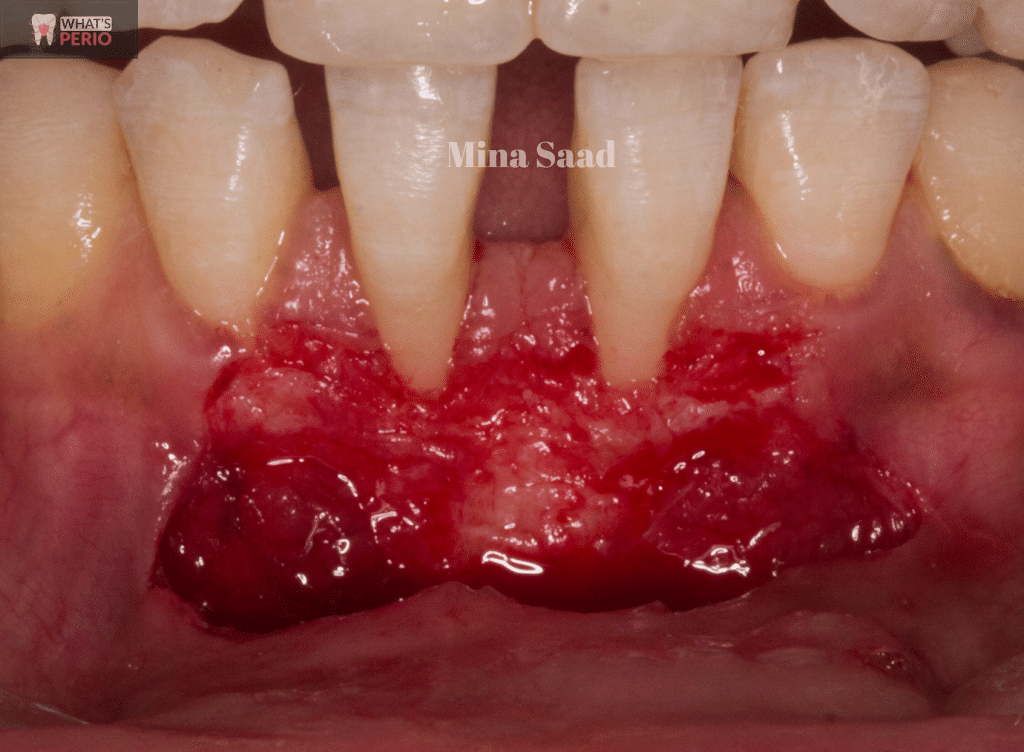

Vascular bed preparation to receive the free gingival graft. "recipient site"

Graft must cover at least 3 mm of the vascular bed (mesial, distal & apical) to the exposed root surfaces..... So the vascular bed should be bigger than the graft size

1-In order for the free gingival graft to survive , regenerate the needed keratinized tissues & avoid its necrosis , a vascular bed was needed to be prepared on the recipient site to give the needed blood supply to the graft through blood vessels bridging between the grafted tissue and the vascular bed as exposed root surfaces are avascular & won’t give any blood supply .

2-The graft must cover at least 3mm of the vascular bed mesial , distal & apical to the exposed root surface…..so the vascular bed size should be bigger than the graft size.

3-3 split thickness horizontal incisions were made at the base of interdental papillae surrounding the 2 central incisors with 2 vertical incisions “ distal to distal papillae of both teeth”

4- 2 vertical incisions were made oblique in direction giving the chance to the vascular bed base to be wider than the top for better blood supply & they should extend apically (4-5) mm beyond mucogingival junction.

5-The strip of the epithelium was dissected revealing the underlying periosteum.